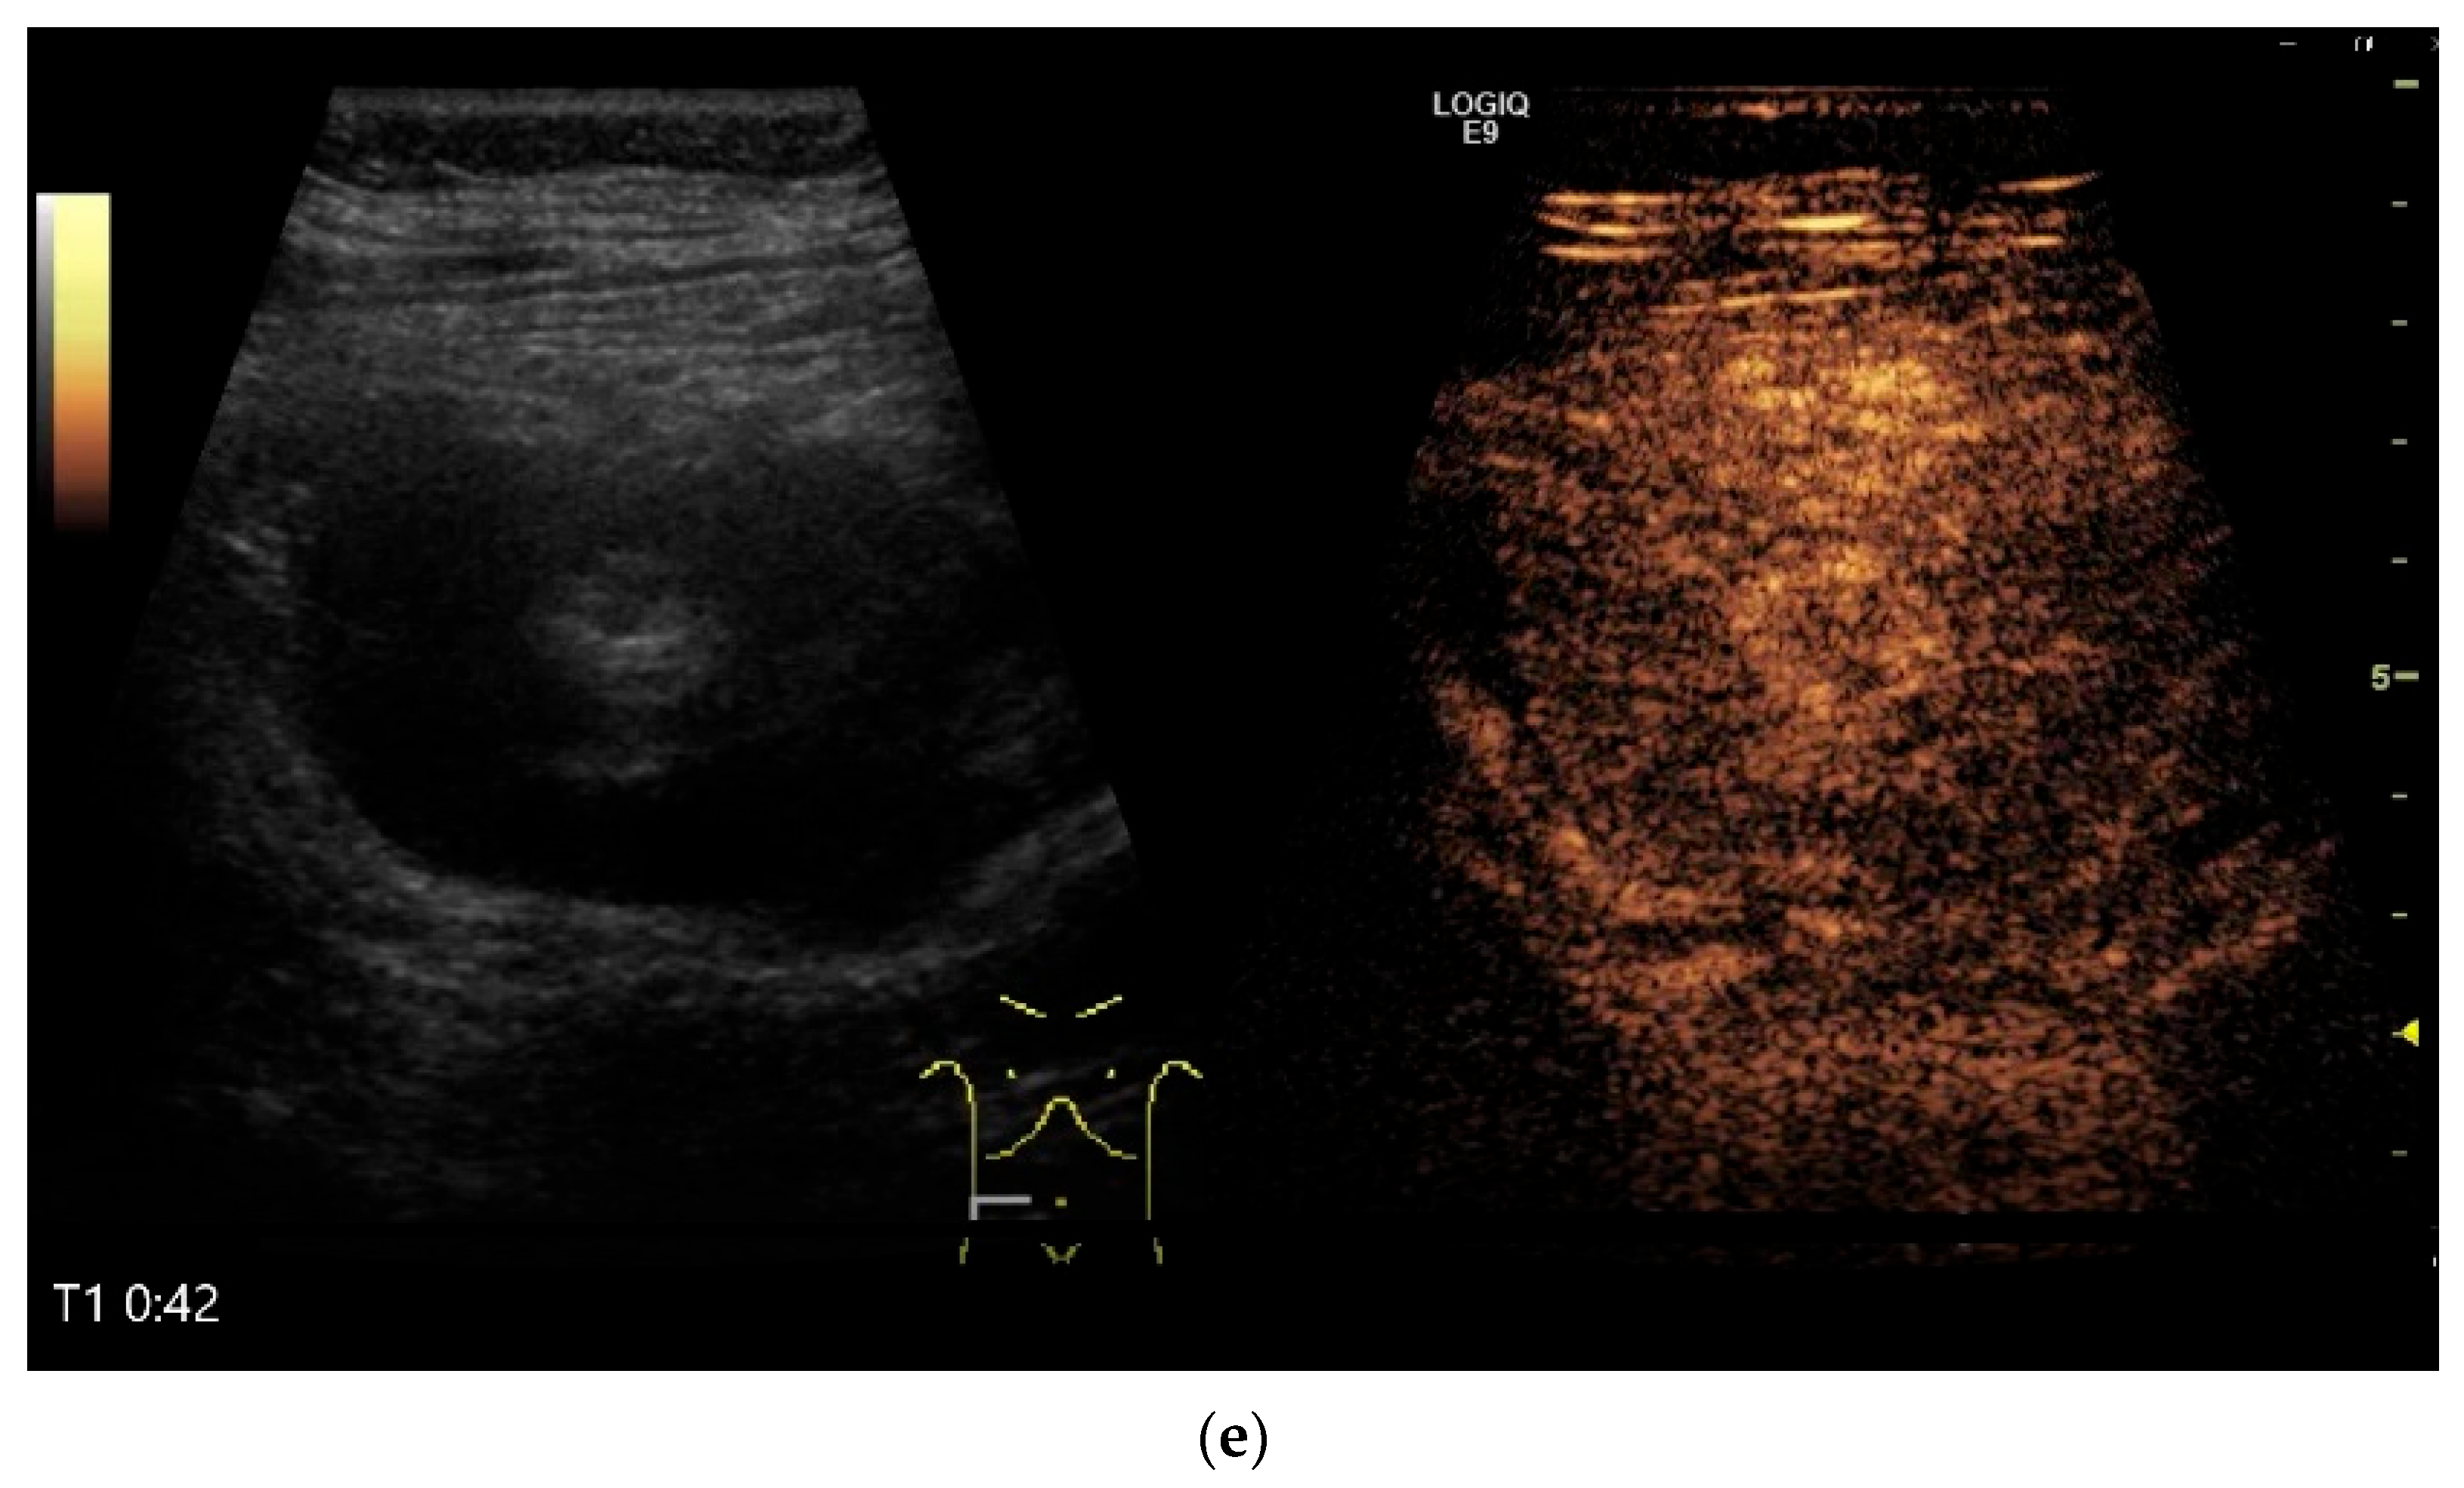

4.6. CEUS

| GIST | Round hypoechoic masses, homogeneous or heterogeneous depending on size. They usually originate from the muscularis propria, which can be difficult to distinguish in US. Small vessels on CDI, hyperenhancement on CEUS. They move with the small intestine and can change position. |

- Multiparametric US, including CDI and CEUS, enhances lesion characterization by assessing vascularity and necrosis, especially in GISTs and neuroendocrine tumors.